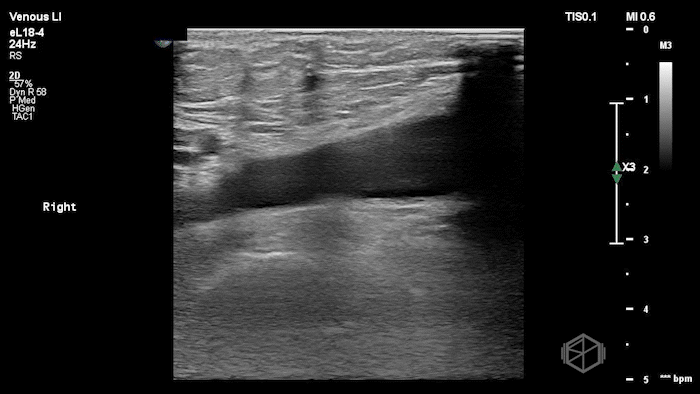

A lower extremity DVT ultrasound performed by Dr. Koutsounadis demonstrated the following:

The POCUS shows a right common femoral vein thrombus. Family members reported that the patient had previously been diagnosed with a DVT very recently and was on apixaban.

The thrombus appeared predominantly hypoechoic to nearly anechoic, making it difficult to appreciate on B-mode imaging alone. However, incomplete compressibility of the vein confirmed the presence of thrombus.

Diagnosis: Right common femoral partially occlusive DVT